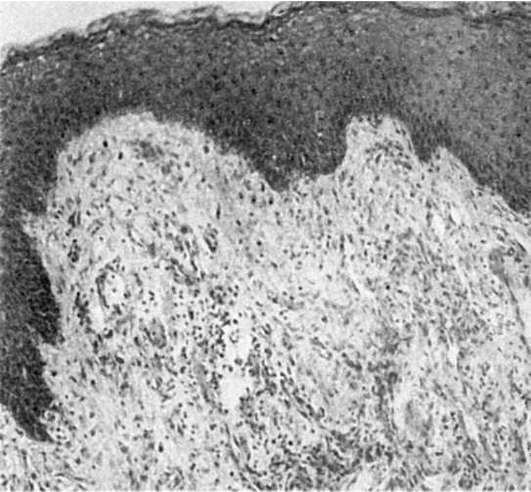

Рис. 354. Пародонтит.

Гладкая и лакунарная резорбция губчатой кости